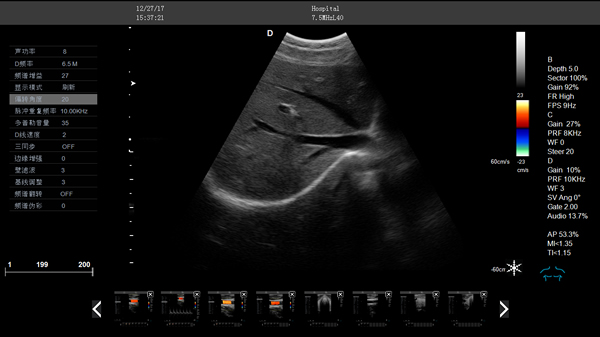

DW-CT580 全數(shù)字彩色多普勒超聲診斷儀

DW-CT580,全數(shù)字彩色多普勒超聲診斷儀,推車式彩超